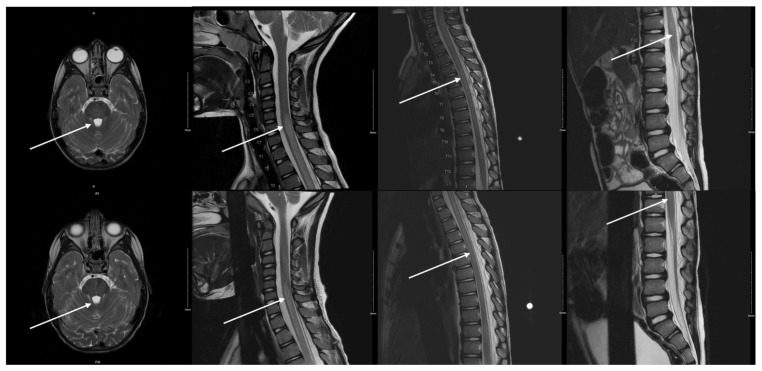

步态障碍在儿科患者可以与广泛的感染性,创伤性,肌肉骨骼和神经学的病因诊断陷阱。此外,孩子们可能很难表达他们的痛苦,也很难检查。这个病例强调了慢下来获取详细病史以及对我们的儿科患者进行彻底检查的重要性,这在繁忙的急诊科可能是具有挑战性的。我们提出一个病例急性横断脊髓炎(ATM)在一个四岁的男性谁提出了一天的跛行和双侧腿痛与负重。看护人报告说可能是日托所里的斗殴造成的远端创伤。神经学检查显示明显异常,包括双侧髌骨反射亢进、双侧下肢无力、阵挛和步态失调。脑和脊柱MRI显示纵向广泛的ATM伴脊髓水肿。尽管缺乏感染前驱症状的证据,但脑脊液感染分析显示肺炎支原体是病原体。静脉注射(IV)甲基强的松龙和阿奇霉素治疗导致出院后几周内所有神经系统后遗症的最终解决。本报告强调了在鉴别以步态疾患为表现的儿科患者时考虑ATM的重要性,以及彻底的神经学检查的重要性,否则诊断将被错过。主题:小儿急诊医学、小儿神经病学、急性横断面脊髓炎、小儿步态障碍。

Gait disturbances in pediatric patients can be wrought with diagnostic pitfalls given the broad infectious, traumatic, musculoskeletal, and neurological etiologies. Furthermore, children can have difficulty communicating their pain and can be hard to examine. This case highlights the importance of slowing down to obtain a detailed history as well as perform a thorough exam in our pediatric patients, which can be challenging in a busy emergency department. We present a case of acute transverse myelitis (ATM) in a four-year-old male who presented with a one-day history of limp and bilateral leg pain with weight bearing. The caretakers reported a possible remote trauma from roughhousing at daycare. Neurological examination revealed significant abnormalities including bilateral patellar hyperreflexia, bilateral lower extremity weakness, clonus, and gait ataxia. A brain and spinal MRI revealed longitudinally extensive ATM with cord edema. Despite the lack of any evidence of infectious prodrome, cerebrospinal infectious analysis revealed Mycoplasma pneumonia as the causative agent. Treatment with intravenous (IV) methylprednisolone and azithromycin therapy led to eventual resolution of all neurological sequelae within a few weeks of discharge. This report emphasizes the importance of considering ATM in the differential of pediatric patients presenting with gait complaints, as well as the importance of a thorough neurologic exam, without which the diagnosis would have been missed.